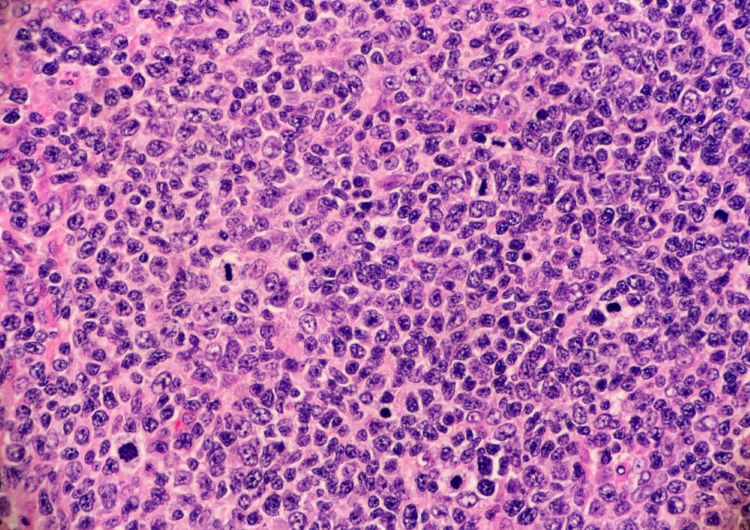

GSK immuno-oncology treatment achieves novel EU approval

The EC’s approval of the immuno-oncology treatment “will define a new standard of care for certain patients with advanced or recurrent endometrial cancer in the EU,” says principal investigator of the RUBY trial.